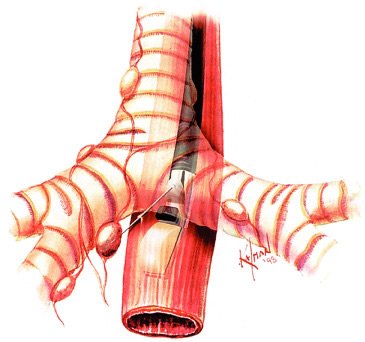

Mobilização do estômago para derivação gástrica subesternal ou substituição esofágica após esofagectomia transiatal. Os vasos gástricos e gastroepiplóicos direitos são preservados, a manobra de Kocher e a piloromiotomia realizadas, e a cárdia seccionada com grampeador e reforço manual. A esofagectomia transiatal é realizada através de uma laparotomia mediana supraumbilical e uma incisão cervical sem toracotomia; entretanto, o esôfago torácico é ressecado atravês da ampliação do hiato diafragmático e do pescoço. O estômago é mobilizado pela secção dos vasos gastroepiplóicos esquerdos e gástricos esquerdos, com preservação das arcadas gastroepiplóica direita e gástrica direita.

Mobilização esofágica durante esofagectomia transiatal sob visualização direta, auxiliada pela ampliação do hiato diafragmático e retração anterior das estruturas mesomediastinais Piloromiotomia e jejunostomia alimentar são realizadas de rotina. Todo o esôfago torácico, do nível das clavículas à cárdia, é ressecado, enquanto há monitoração cuidadosa da pressão intra-arterial para evitar hipotensão prolongada pela mobilização cardíaca durante a dissecção esofágica transiatal .

Após completar a esofagectomia transiatal para tumor localizado no terço distai, é confeccionado o tubo gástrico com o emprego de grampeamento mecânico da grande curvatura, ressecando o máximo de estômago possível distai ao tumor macroscópico. O restante do estômago é, então, posicionado no mediastino posterior no leito esofágico original e anastomosado ao esôfago cervical O grampeador cirúrgico é utilizado para a confecção do tubo gástrico a partir da grande curvatura gástrica com preservação de todo o comprimento.

Após a esofagectomia transiatal e a piloromiotomia, o estômago é mobilizado através do mediastino posterior, o fundo suturado à fascia cervical pré-vertebral, e a esofagogastrostomia término-lateral é, então, realizada

O grampeador é fechado, com aproximação das pás; mas, antes de dispará-lo, realizam-se dois pontos de suspensão em cada lado, entre o estômago anterior e o esôfago adjacente. B, Quando a lâmina do grampeador é avançada, a "parede comum" entre o esôfago e o estômago é seccionada, criando-se uma anastomose ipsilateral de 3 cm de extensão. Então, a sutura dos ângulos é feita em cada lado da gastrotomia. C, A gastroto-mia e o esôfago aberto remanescente são aproximados em duas camadas

O estômago é mobilizado através do mediastino posterior no leito esofagico original e anastomosado (manual ou por grampeamento) ao esôfago cervical.

O estômago normal, adequadamente mobilizado, alcança o pescoço em todos os pacientes.